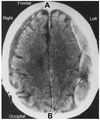

Label this.

What are the sutures of the skull and what are the joining points you need to know?

What suture is this?

Coronal suture

Sagittal suture

Lambdoid suture (parieto-occipital suture)